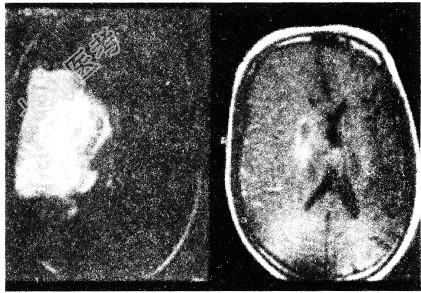

- 单项选择题3.核磁检查结果(见图)首先考虑诊断

A、脑梗死

B、脑囊肿

C、脑膜瘤

D、高血压脑出血

E、胶质瘤